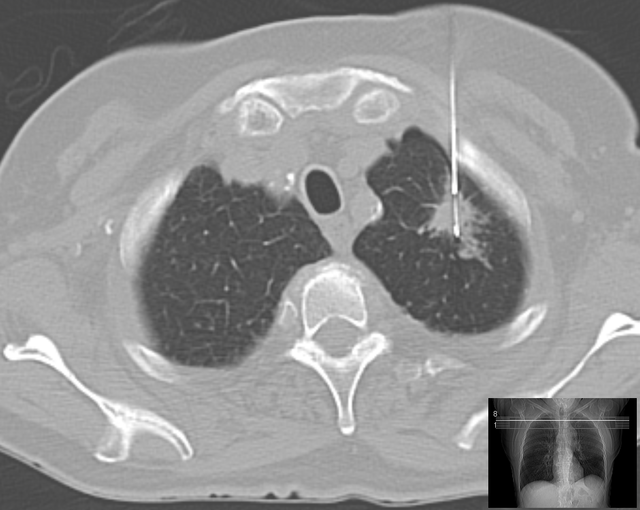

Uma conquista notável nessa área é o recente anúncio do Massachusetts Institute of Technology (MIT) e do Mass General Hospital (MGH), dos EUA, sobre o desenvolvimento de um modelo de aprendizado profundo chamado “Sybil” que pode ser usado para prever o risco de câncer de pulmão, usando dados a partir de apenas uma única tomografia computadorizada.

Os líderes do estudo afirmam que “um modelo de aprendizado profundo avaliando todos os dados volumétricos de LDCT [Low Dose Contrast CT] poderia ser construído para prever o risco individual sem a necessidade de dados demográficos ou clínicos adicionais”.

O modelo começa com um princípio básico: “As imagens LDCT contêm informações que predizem o risco futuro de câncer de pulmão além dos recursos atualmente identificáveis, como nódulos pulmonares”. Portanto, os desenvolvedores procuraram “desenvolver e validar um algoritmo de aprendizado profundo que prevê o risco futuro de câncer de pulmão em até 6 anos a partir de uma única varredura de LDCT e avaliar seu potencial impacto clínico”.